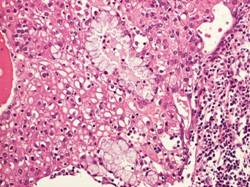

Aspetto istologico:

Il carcinoma mucoepidermoide è composto da vari tipi di cellule:

Cellule Basaloidi,

Cellule Intermedie,

Cellule Epidermoidi,

Cellule Colonnari,

Cellule Mucoidi,

Nell immagine sottostante è riportato un caso di carcinoma mucoepidermoide a basso grado che infiltra il tessuto osseo, per ricordare che anche le forme di basso grado hanno capacità invasiva. L intervento chirurgico tempestivo è importante.